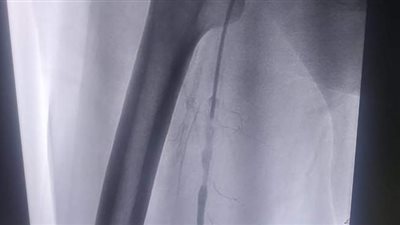

اعلن الدكتور سعد مكي وكيل وزارة الصحة بالدقهلية عن نجاح فريق طبي بإنهاء معاناة طفلة تبلغ من العمر 11 عاما كانت تعاني من إفراط مستمر في نشاط الغدد العرقية لليدين نتيجة وجود خلل في التحكم العصبي للعصب السمبثاوي المسئول عن افراز العرق اللازم لتنظيم درجة حرارة الجسم والذي أثر سلبا على ممارستها للحياة الطبيعيه اليومية .